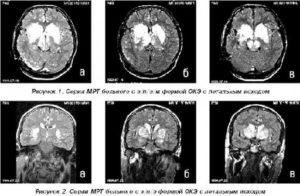

Одиночное образование в левой височной доле. Метастаз рака молочной железы. Первичный отклик на стереотаксическую лучевую терапию (кибер нож) сменился повторным ростом опухоли после окончания лечения